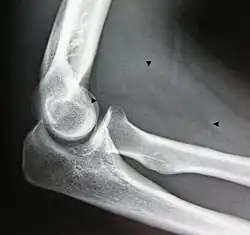

A physical exam is typically the easiest way to diagnose it. Rarely, a tissue biopsy or imaging may be required. The imaging modality of choice is magnetic resonance imaging (MRI) because it has superior sensitivity of distinguishing it from liposarcoma as well as mapping the surrounding anatomy.[22]

-

X-ray of a lipoma -

X-ray showing lipoma -